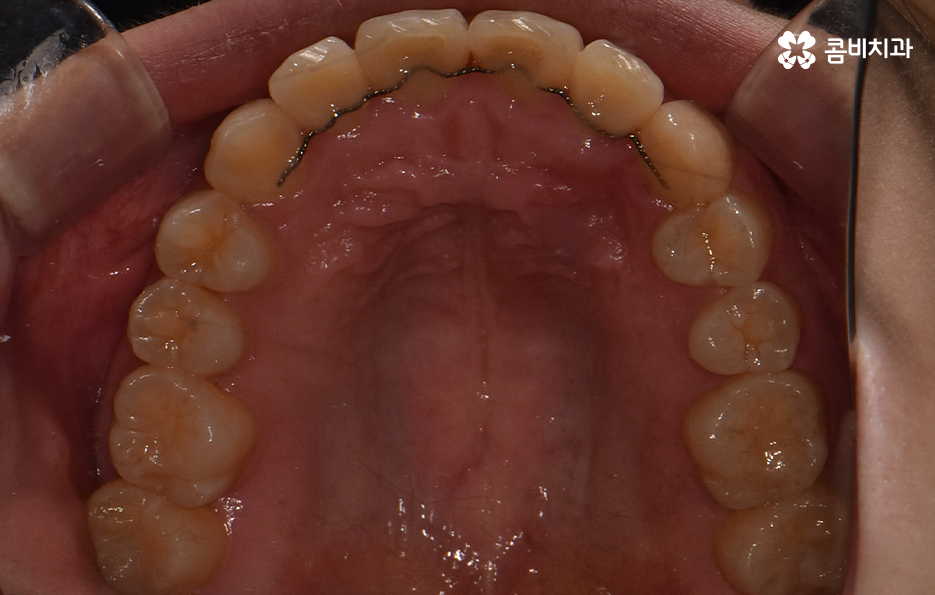

오늘 덧니 비발치 교정 사례로 보시는 환자분의 경우에는 윗니와 아랫니 앞니 부분에 조금씩 덧니가 있는 상태로 덧니를 제외하면 대체적으로 치열 상태는 고른 편이며 덧니 교정 사례 중에서는 돌출입도 함께 개선해야 하는 경우가 많지만 위 환자분의 경우에는 돌출입의 정도가 양호했고 입술라인 역시도 정상 범위에 가까웠기 때문에 발치를 필요로 하지 않았지만 치아의 이동 공간과 보다 자연스러운 입술라인 그리고 얼굴형과의 조화를 고려하여 악궁 확장과 어금니 후방 이동을 적절히 활용하여 교정 치료가 진행되었다고 볼 수 있어요

대부분의 발치 교정의 경우 작은 어금니를 발치하여 치아의 이동 공간을 확보하는 경우가 많다면 덧니 비발치 교정의 경우 발치교정 만큼은 아니더라도 치아를 이동 시킬 공간을 약간이라도 확보해야 하기 때문에 악궁 확장이나 치간삭제를 하는 경우가 있으며 어금니 후방 이동이 필요할 경우에는 사랑니 발치를 해야할 수 있어요